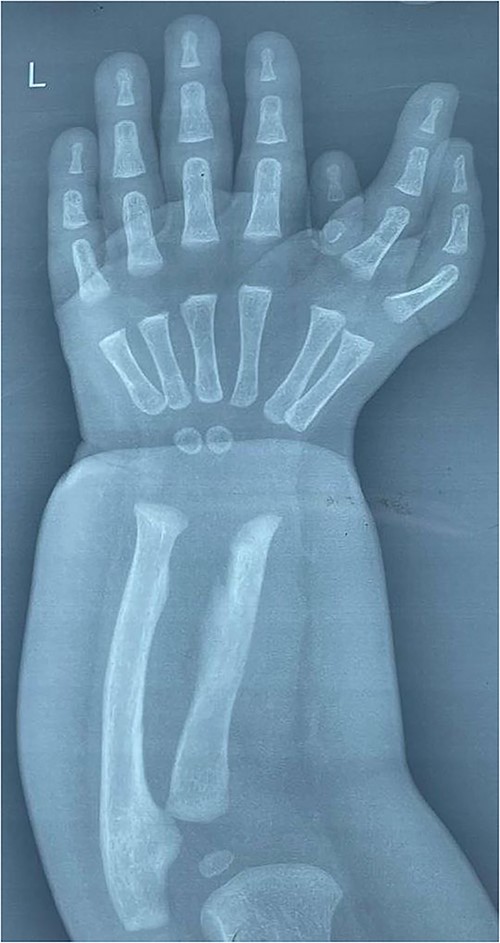

The child was prepared for surgery under general anesthesia.

We used the principles of pollicisation to reconstruct the thumb by maintaining the largest and most functional of the accessed fingers and do intrinsic muscle transfers.

We did ray amputation to finger ulnar to the most radial digit in addition to excision of the rudimentary digit to preserve adequate first web space, in addition to repair of interosseous muscles with augmentation of the interosseous power as thumb abductor by suturing of flexor tendon of the amputated digit to them, skin closure was done with vicryl suture (Fig. 3).